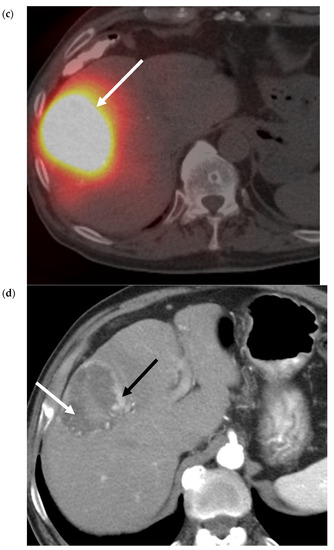

- Riaz, A.; Gates, V.; Atassi, B.; Lewandowski, R.; Mulcahy, M.F.; Ryu, R.K.; Sato, K.T.; Baker, T.; Kulik, L.; Gupta, R.; et al. Radiation Segmentectomy: A Novel Approach to Increase Safety and Efficacy of Radioembolization. Int. J. Radiat. Oncol. 2011, 79, 163–171. [Google Scholar] [CrossRef]

- Padia, S.A.; Kwan, S.W.; Roudsari, B.; Monsky, W.L.; Coveler, A.; Harris, W.P. Superselective Yttrium-90 Radioembolization for Hepatocellular Carcinoma Yields High Response Rates with Minimal Toxicity. J. Vasc. Interv. Radiol. 2014, 25, 1067–1073. [Google Scholar] [CrossRef] [PubMed]

- Lewandowski, R.; Gabr, A.; Abouchaleh, N.; Ali, R.; Al Asadi, A.; Mora, R.; Kulik, L.; Ganger, D.; Desai, K.; Thornburg, B.; et al. Radiation Segmentectomy: Potential Curative Therapy for Early Hepatocellular Carcinoma. Radiology 2018, 287, 1050–1058. [Google Scholar] [CrossRef]